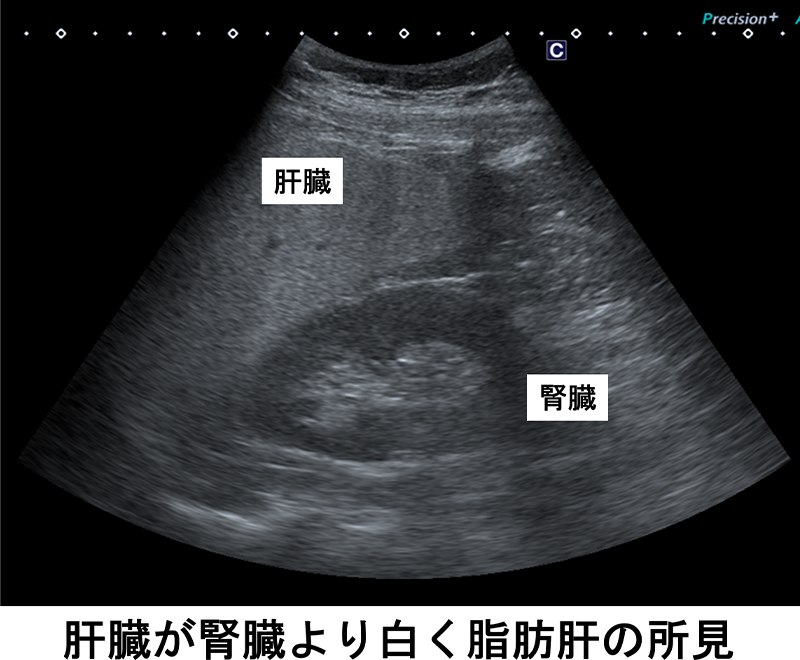

腹部エコーでは、肝臓・胆のう・膵臓・腎臓・脾臓などの臓器を調べます。また、腸閉塞や腸炎などについても状態の把握や診断の参考となります。胆石や腫瘍、炎症の有無などを調べるだけでなく、当院では特に脂肪肝の評価に力を入れています。

脂肪肝は、日本人の約3割にみられるといわれ、放置すると脂肪肝炎や肝硬変、肝がんへと進行する可能性があります。当院導入のエコーでは、肝臓にどのくらい脂肪が蓄積しているかを定量的に数値化でき、画像だけでは捉えにくい早期の脂肪肝の評価にも役立ちます。健診で肝機能異常(AST・ALT上昇など)を指摘された方には、採血だけでなく腹部エコーでの評価をおすすめします。

- 脂肪肝